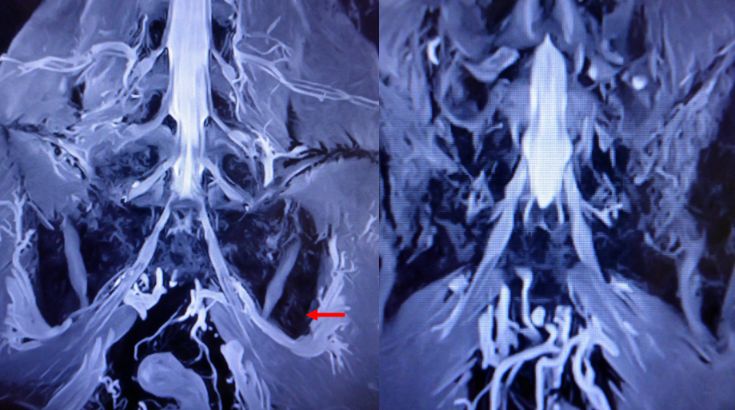

- 영상 검사 : MRI, X-ray 등을 통해 디스크 이상등과 같은 다른 원인의 가능성을 배제합니다.